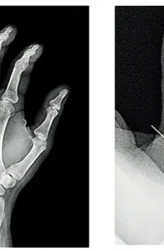

И опять у невролога возникли сомнения относительно верности интерпретации исследования, в связи с чем врач обратился к врачу МРТ с диском. И опять не зря! По снимкам выявлено выраженное повреждение сухожилий передней большеберцовой и длинной малоберцовой мышц, что и прояснило причину нарушения движений в левой стопе. На рисунке стрелками указаны поврежденные сухожилия — вначале целые, потом разрыв, затем вновь нормальная структура.